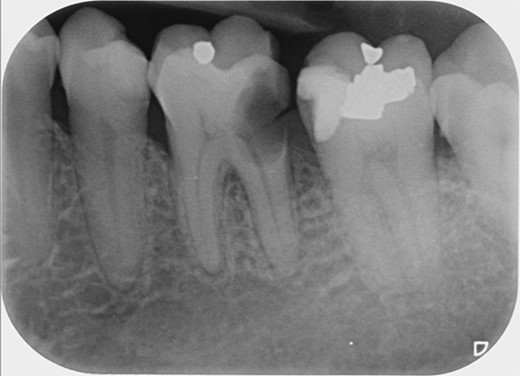

A 59-year-old male patient presented with a complaint of pain while biting on his lower left posterior teeth. Clinical examination revealed an extensive amalgam restoration on the lower left first molar (tooth 36) with a fractured restoration and secondary caries on the lingual aspect. The tooth was non-responsive to thermal testing and electrical pulp sensibility testing (EPT) and was tender to percussion. Radiographic examination showed radiolucency beneath the restoration on the mesial root surface, indicative of caries, along with furcation involvement and peri-radicular radiolucency. The tooth was diagnosed with pulpal necrosis and symptomatic apical periodontitis associated with extensive root caries (Fig. 6 and 7).

Periapical radiograph of tooth 36 shows large radiopacity, indicating a restoration on the crown extending to the mesial root surface. Radiolucency was detected beneath restoration on the mesial root surface, indicating caries. Peri-radicular radiolucency was observed in the furcation region.